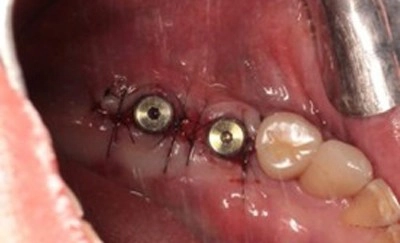

2. 3D斷層掃描再評估 與 人工牙根植入

- 精準執行: 醫師根據術前3D電腦斷層掃描的數據,精準計算骨密度、人工牙根的位置、角度與深度,將兩支人工牙根穩穩地植入重建完成的骨組織中。

- 術後呈現: 圖片中可見,植體穩定地固定在齒槽骨內,並進行了細緻的傷口縫合,等待骨整合的完成。